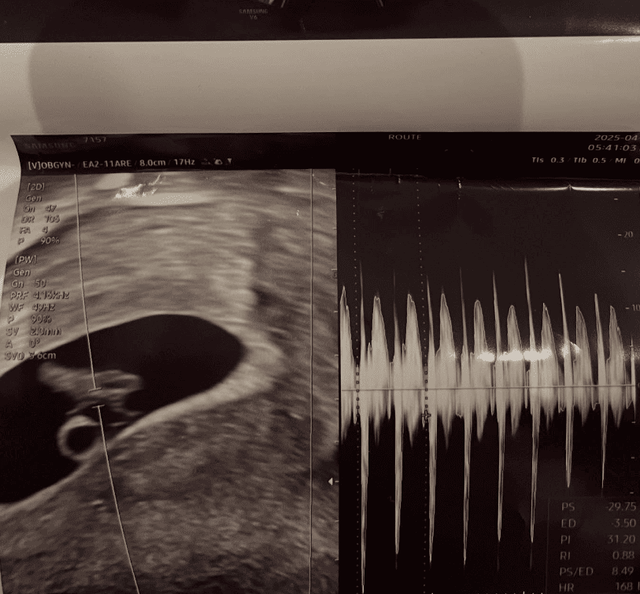

서은우는 “아빠 된 거 축하해”라는 짧지만 강렬한 문구와 함께 초음파 사진을 게시했고, 곧이어 남자친구로 추정되는 인물과 다정하게 찍은 사진을 추가로 공개했습니다.